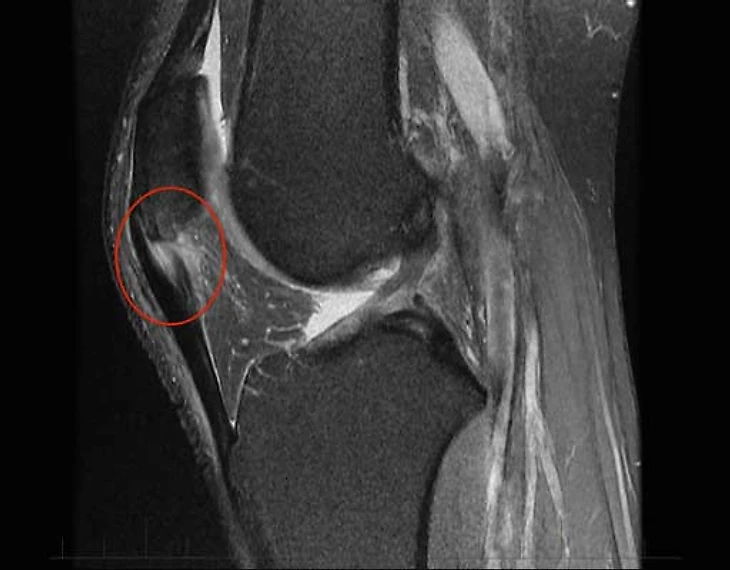

Вы, наверное удивитесь, но МРТ, в отличие от большинства других мышечно-сухожильных не всегда является лучшим методом диагностики. В случае тендинопатии Ахилла или четырехглавой мышцы УЗИ позволяет не только поставить диагноз, но и подробнее оценить степень изменений. Но это требует определенных навыков от спортивного врача.

Вот, как это примерно выглядело в случае Маслова.

Как мы видим, УЗИ позволяет точнее оценить степень изменений в сухожилии, особенно это касается неоваскуляризации. Плюс, это динамический метод, то есть мы можем попросить пациента двигать ногой, сокращать мышцы бедра и оценить, как на это реагирует сухожилие. В случае МРТ мы можем оценить лишь статичную картинку. Но и у МРТ есть свои плюсы — больший объем оцениваемых тканей; позволяет оценить еще и состояние сустава, куда ультразвуковой сигнал уже не добирается. Плюс, УЗИ хороший метод только при оценке поверхностно лежащих тканей. В случае тендинопатии в других областях МРТ может оказаться точнее и более предпочтительным методом.